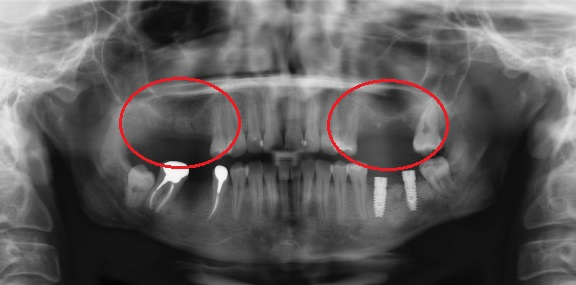

• Если толщина верхней челюстной кости меньше 10 мм и гайморовая пазуха анатомически расположена близко, то во время установки импланта её можно повредить. Вот почему сначала необходимо увеличить объём костной ткани.

Операции предшествует тщательная диагностика при помощи компьютерной томографии. Врач вычисляет высоту кости от её низа до гайморовой пазухи. Если он приходит к выводу, что при такой высоте кость не выдерживает имплантата с коронкой, назначается операция. Затем проводится визуальное обследование с целью убедиться в готовности ротовой полости к синус лифтингу.